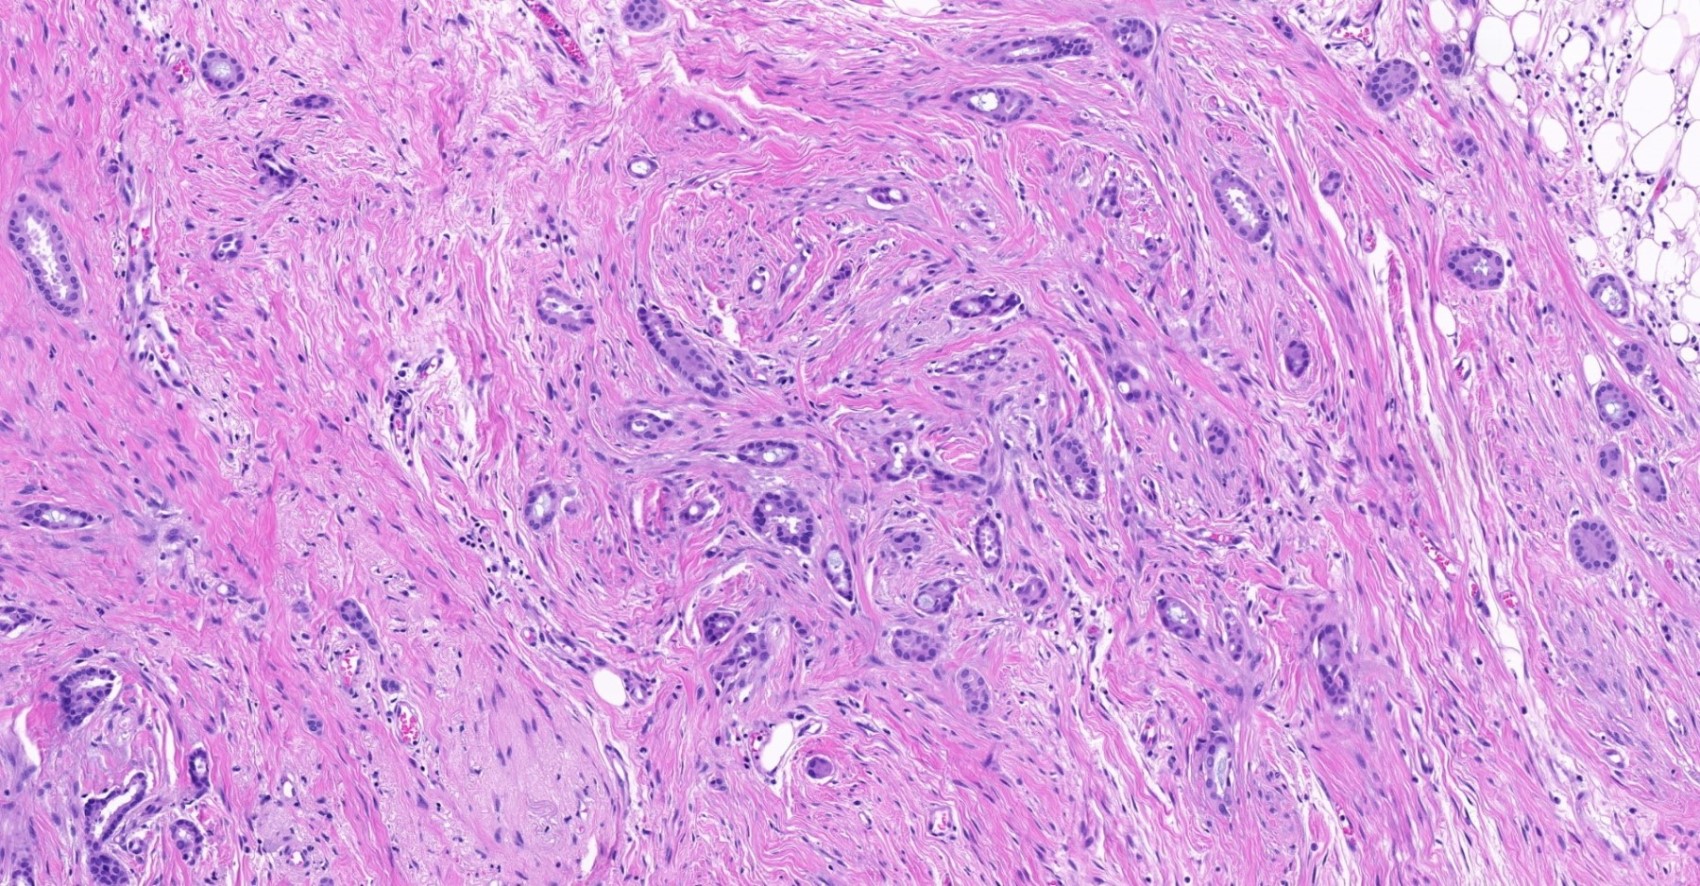

Microscopic (histologic) description

- Histological features of IBC NST vary considerably from case to case and even within the same case

- Margins vary from highly infiltrative, permeating the surrounding tissue, to continuous pushing margins

- Architecture varies from sheets, nests, clusters, cords or individual cells (but lacks the cytomorphological characteristics of invasive lobular carcinoma)

- Tubular formations are prominent in well differentiated tumors but absent in poorly differentiated tumors

- 2 distinct growth patterns exist:

- Tumors characterized by small cancer nests accompanied by marked fibrosis (desmoplastic / scirrhous); this type diffusely infiltrates the surrounding tissue as an irregular shaped spiculated mass

- Elastosis involves stroma, wall of vessels and ducts and causes grossly noted chalky streaks

- Often ductal carcinoma in situ (DCIS) (up to 80%)

- In some cases, DCIS is extensive

- Associated DCIS is usually of same nuclear grade as the invasive carcinoma

- Perineural invasion (28%)

- No myoepithelial cell lining (as seen in DCIS or benign lesions)

Microscopic (histologic) images

Contributed by Julie M. Jorns, M.D., Kristen E. Muller, D.O., Gary Tozbikian, M.D. and Emad Rakha, M.D.